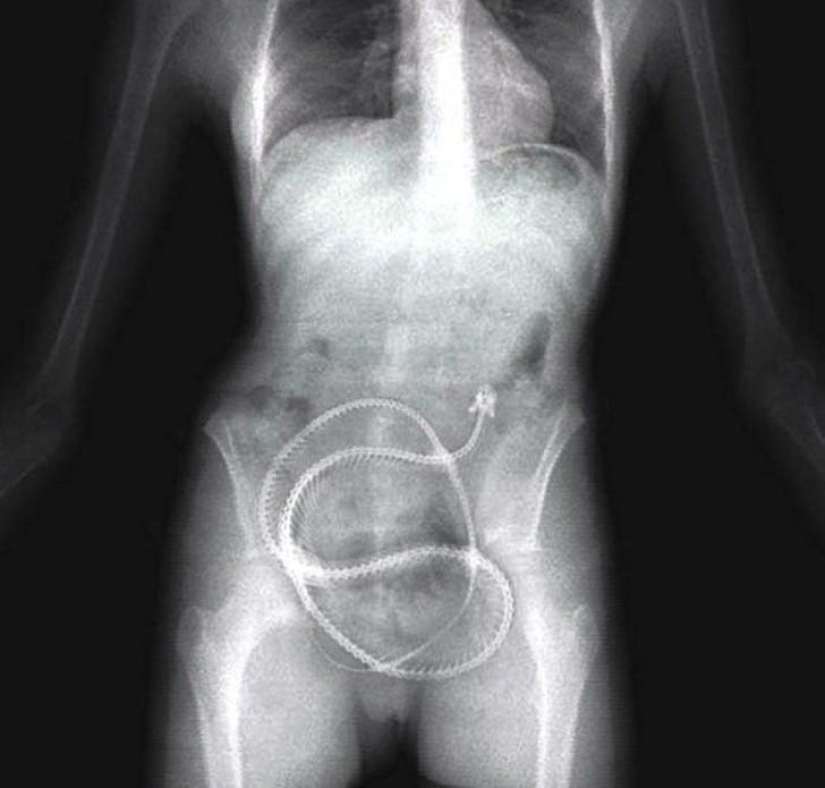

Teléfono móvil.